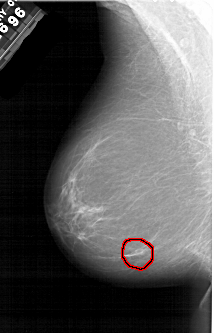

A_1308_1.LEFT_MLO

LEFT_MLO LINES 5986 PIXELS_PER_LINE 3841 BITS_PER_PIXEL 12 RESOLUTION 43.5 OVERLAY

FILE: A_1308_1.LEFT_MLO.OVERLAY

TOTAL_ABNORMALITIES 1

ABNORMALITY 1

LESION_TYPE MASS SHAPE LOBULATED MARGINS ILL_DEFINED

ASSESSMENT 4

SUBTLETY 3

PATHOLOGY BENIGN

TOTAL_OUTLINES 1

BOUNDARY